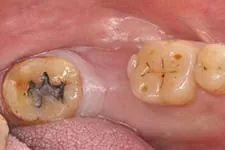

3. 即拔即種

打破傳統即拔即種(又叫立即植牙),拔牙後立刻植牙。患者可在拔牙後立即植入人工植體,並立刻裝戴假牙。讓你治療當天就能擁有美觀的門面。